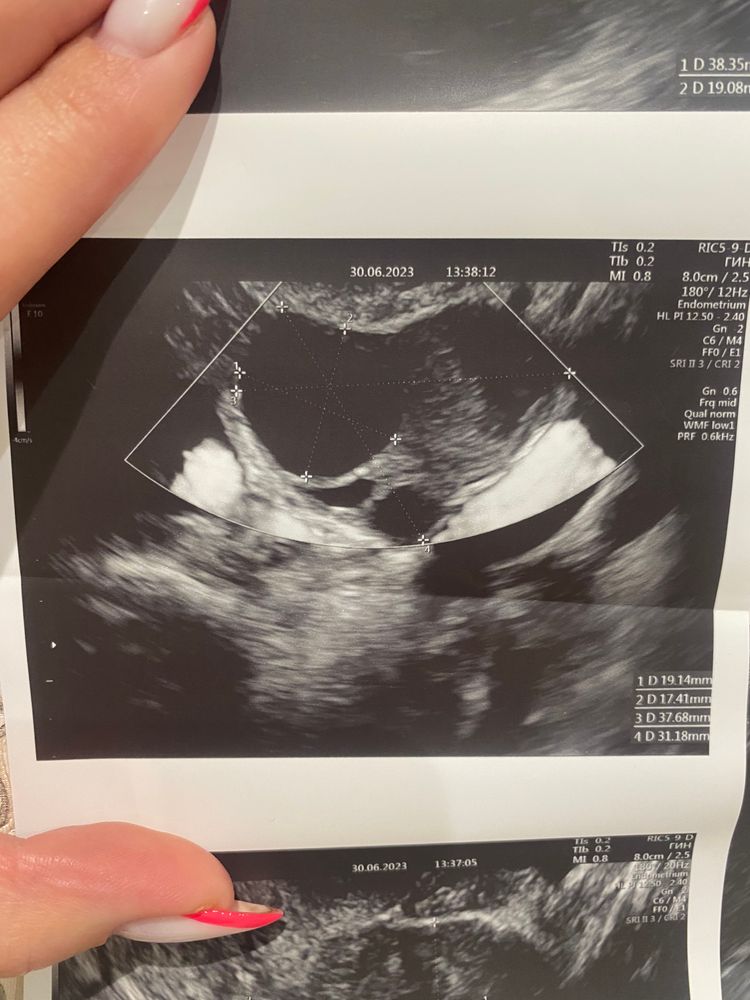

Девочки , подскажите пожалуйста кто разбирается в узи

Да нет никаких кист, это доминантный фолликул. Размер 19х17. Нормальный преовуляторный фолик. У меня таких фоток тьма, желтое тело вообще по другому выглядит

Виктория, думаю просто когда неочевидно они только предполагают. Сказано фоллик должен быть идеально круглый - значит если не круглый, то ЖТ) почему киста только не поняла, размер то нормальный)

Это не жёлтое тело. Это дф. Отслеживали овуляцию по УЗИ несколько месяцев и жёлтое тело оно конечно совсем другое.

По-моему у вас фолликулярная киста, судя по узи яичника и по эндометрию

Девочки че то с мамой поговорила и за переживала климакс в 36 лет у неё тип начался( УЗИ после бхб. Киста, эндометриоз?